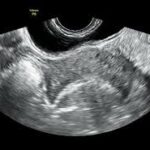

El desarrollo de herramientas tecnológicas para la obtención de imágenes y datos fisiológicos del corazón ha experimentado avances significativos gracias a la evolución de técnicas de diagnóstico por imagen. El ecocardiograma, en particular, ha jugado un papel crucial en la visualización del corazón y en la evaluación de su funcionamiento, permitiendo obtener imágenes detalladas de sus estructuras y movimientos. Este tipo de diagnóstico no invasivo ha tenido un impacto fundamental en la medicina cardiovascular, dado que proporciona una forma eficaz y segura para estudiar el corazón en tiempo real.

La llegada del ecocardiograma bidimensional marcó un hito significativo en la evolución de la imagenología cardíaca, ya que permitió obtener representaciones visuales más detalladas y precisas de las estructuras del corazón en tiempo real. Este avance no solo transformó la forma en que se capturaban las imágenes, sino que también planteó nuevos desafíos en cuanto a su registro y almacenamiento. Para satisfacer esta necesidad, los investigadores y profesionales médicos comenzaron a explorar diferentes métodos que permitieran la grabación de las imágenes bidimensionales de manera eficaz y accesible.